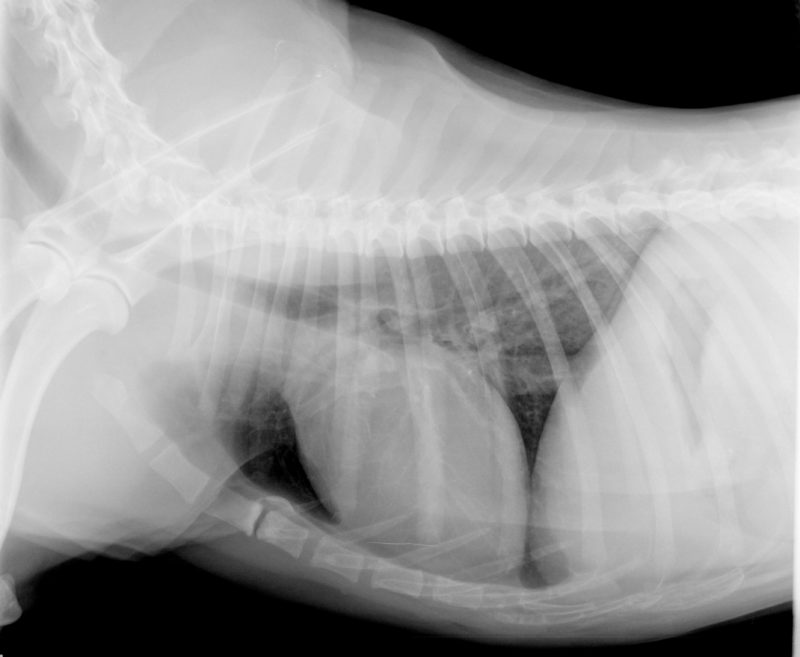

Der erste Schritt der weiterführenden Diagnostik war eine Blutuntersuchung. So können zum Beispiel ein niedriger Blutzucker oder Elektrolytverschiebungen zu Krampfanfällen führen. Wichtig ist auch die Ammoniak-Bestimmung. Vor allem bei sehr jungen Hunden kann eine angeborene Gefäßmissbildung (Lebershunt) zu Krampfanfällen führen. Dabei umgeht das Blut aus dem Darm das Lebergewebe und wird durch ein Gefäß („Shunt“) direkt zur Hauptvene geleitet. Dadurch kann das Blut in der Leber nicht „entgiftet“ werden und die Giftstoffe gelangen in das Gehirn und können zu Krampfanfällen führen. Einer dieser giftigen Stoffe ist Ammoniak, dessen Bestimmung eine schnelle Beurteilung der Leberfunktion ermöglicht. Ergänzend wurden die Schilddrüsenwerte bestimmt. In einer Ultraschalluntersuchung von Ben wurden alle Organe in seinem Bauch genau untersucht. Zur Beurteilung von Herz und Lunge wurde ein Röntgenbild angefertigt (Abbildung 3).